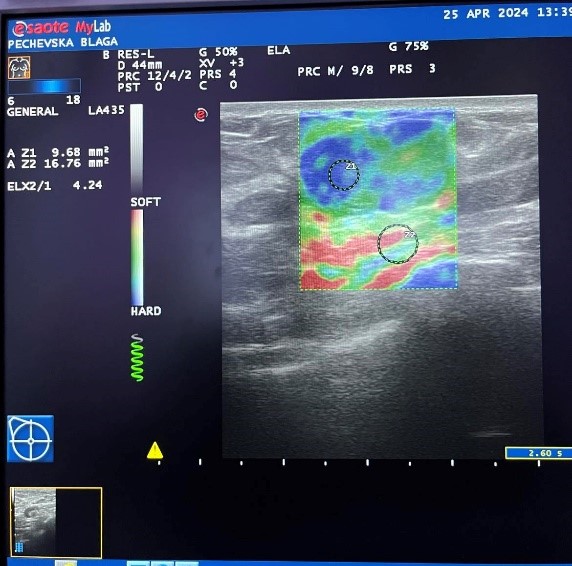

We use strain elastography as semi-quantitative method with ESAOT/ elastography ultrasound, multifrequency probe 5-18 Mhz.

Strain Elastography (SE) determines tissue stiffness by determining the SR – ratio of stiffness in the nodule to the surrounding healthy breast tissue and is calculated automatically by a built-in software program in the ultrasound device.

In this study evaluating SR, the cut-off value for the differentiation of benign and malignant lesions was 3.

Sonoelastography achieves maximum specificity and accuracy, in ranges between 2 and 4.

Figure 3. Inv. Intraductal Breast Carcinoma-MG.

Figure 4. Inv. Intraductal Breast Carcinoma (same patient) – Sonoelastography, US